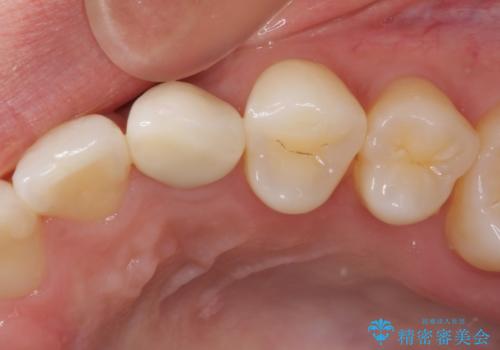

前歯のデコボコが強かったため、上の奥歯を後方に動かす量が多くなり、結果として2年以上の治療期間を擁することとなりました。

インプラント治療は当初の狙い通り、矯正治療期間中に行い、スムーズに処置を進めることができました。

歯並びが整ったことで治療前に認められた歯肉炎は全くなくなり、患者様には大変満足していただきました。